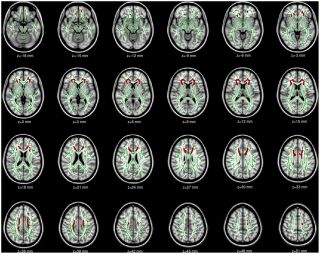

Gray matter atrophy Grey matter is responsible for controlling movement, memory & emotions. A study scanned someone's brain addicted to phone usage & found lower volume of grey matter with their brains resembling the physical shape & size of drug users. ncbi.nlm.nih.gov/pmc/articles/P…

Gray matter atrophy

Grey matter is responsible for controlling movement, memory & emotions.

A study scanned someone's brain addicted to phone usage & found lower volume of grey matter with their brains resembling the physical shape & size of drug users.